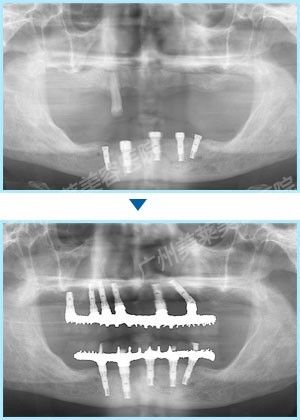

陳回英阿姨在美萊 手術(shù)完成了全口16顆牙種植過程

根據(jù)方案,廣州美萊為陳阿姨上下各種植了8顆牙,手術(shù)中采用即拔即種、植骨、蓋膜、上頜竇提升技術(shù)同步進(jìn)行,這樣可確保種植后她能恢復(fù)全口真牙的咬合功能,吃東西完全沒有問題。 手術(shù)完成了全口16顆牙的種植!